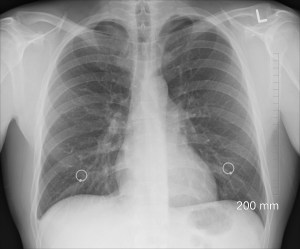

You have a couple of options here. One would be a stab wound into the right side of the chest. This could partially collapse a lung and cause some bleeding as well. Think of the lung as a balloon. A small nick to the lung could cause it to slowly leak air into the chest, keeping the character alive for a few hours, but killing him in the end if the collapsed lung isn’t treated. The more collapsed the lung is, the less it is able to function. The more air that accumulates in the chest, the more it will push other structures.

We call this a tension pneumothorax.

Imagine the right chest is now full of air. Air will keep building unless it is given a way out (like a chest tube) and can actually squish the heart and lungs on the other side of the chest to the point where the heart may not beat anymore.

If a tension pneumothorax is left untreated, this will cause the patient to die. They may die from blood loss, or low oxygen levels, or from the heart being impinged to the point where it can no longer beat.

What signs and symptoms would a patient with a collapsed lung (pneumothorax) have? What’s the difference between and sign and symptom?